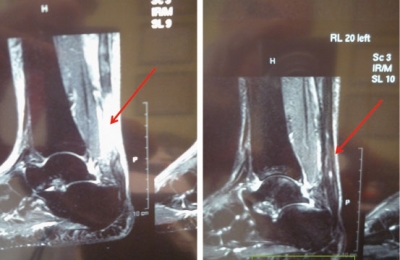

- Lesiones de ligamentos de la rodilla u otras articulaciones

- 2003: …En ligamentoplastias del LCA (lig. cruzado anterior).

- Radice F. et al. Uso de concentrado autologo rico en factores de crecimiento en la reconstruccion del LCA. Revista Argentina de Artroscopia 15:31-40. 2008

- Sánchez M, Azofra J, Anitua E, Andía I, Padilla S, Santisteban J, Mujika I.Plasma Rich in Growth Factors to treat an articular cartilage avulsion: a case report. Med Sci Sports Exer 2003;35:1648-1652.